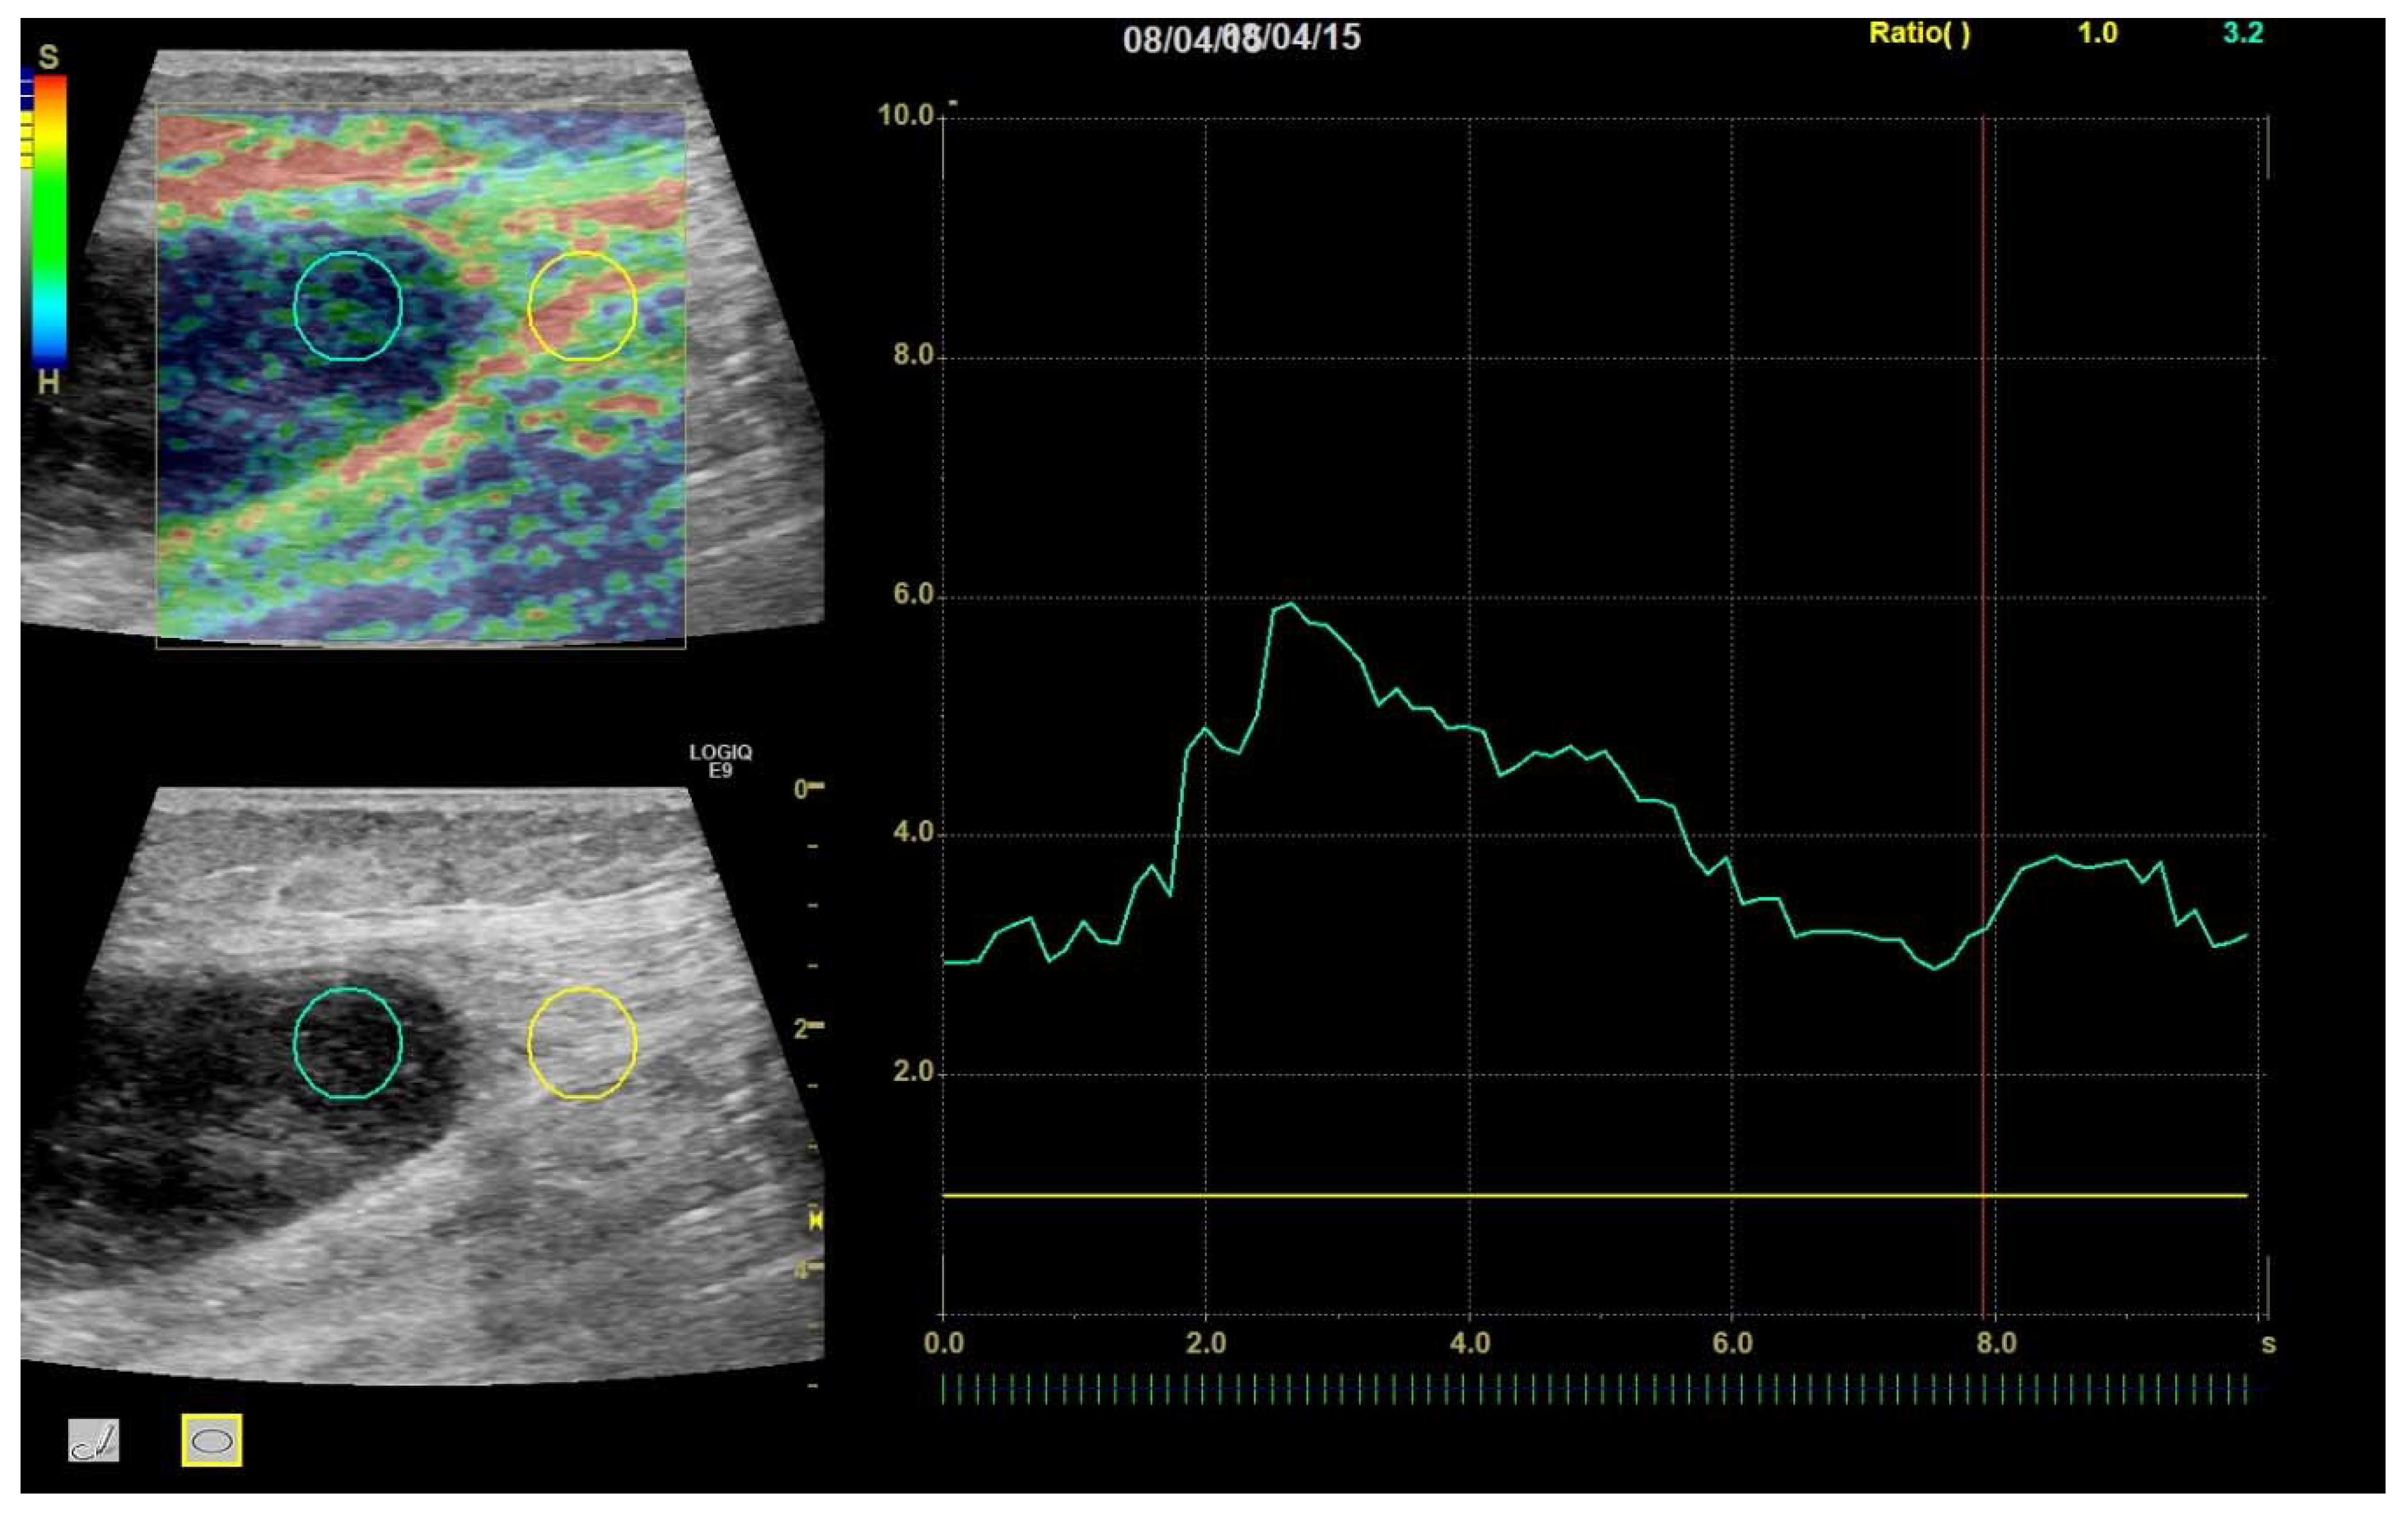

Then, an SR was calculated for each frame by the ultrasound system from two circular or ovoid ROIs placed by the investigators—one tumor ROI inside the tumor and one reference ROI in nearby reference tissue. The tumor ROI was made as large as possible to ensure representability of the tumor, while avoiding obvious cystic areas, and while keeping a small distance to the tumor border to ensure that no reference tissue would be included. The reference ROI was placed outside the tumor boundary in nearby reference tissue at the same depth as the tumor, but tumor ROI and reference ROI were not necessarily of the same size, as ROI size has been shown to not affect SR [18]. Reference soft tissues were predominantly muscular, fatty, or connective tissues, and were selected to be of identical composition with the tumor where possible. For each clip, a mean SR for the entire 10 s clip was calculated (Figure 4).

Figure 4. A 96-year-old female with myxoma. Region of interest (ROI) placement in tumor (left circle) and reference tissue (right circle). Tumor scored a TES of 4 and an average SR over the 10 s cine clip of 3.97.